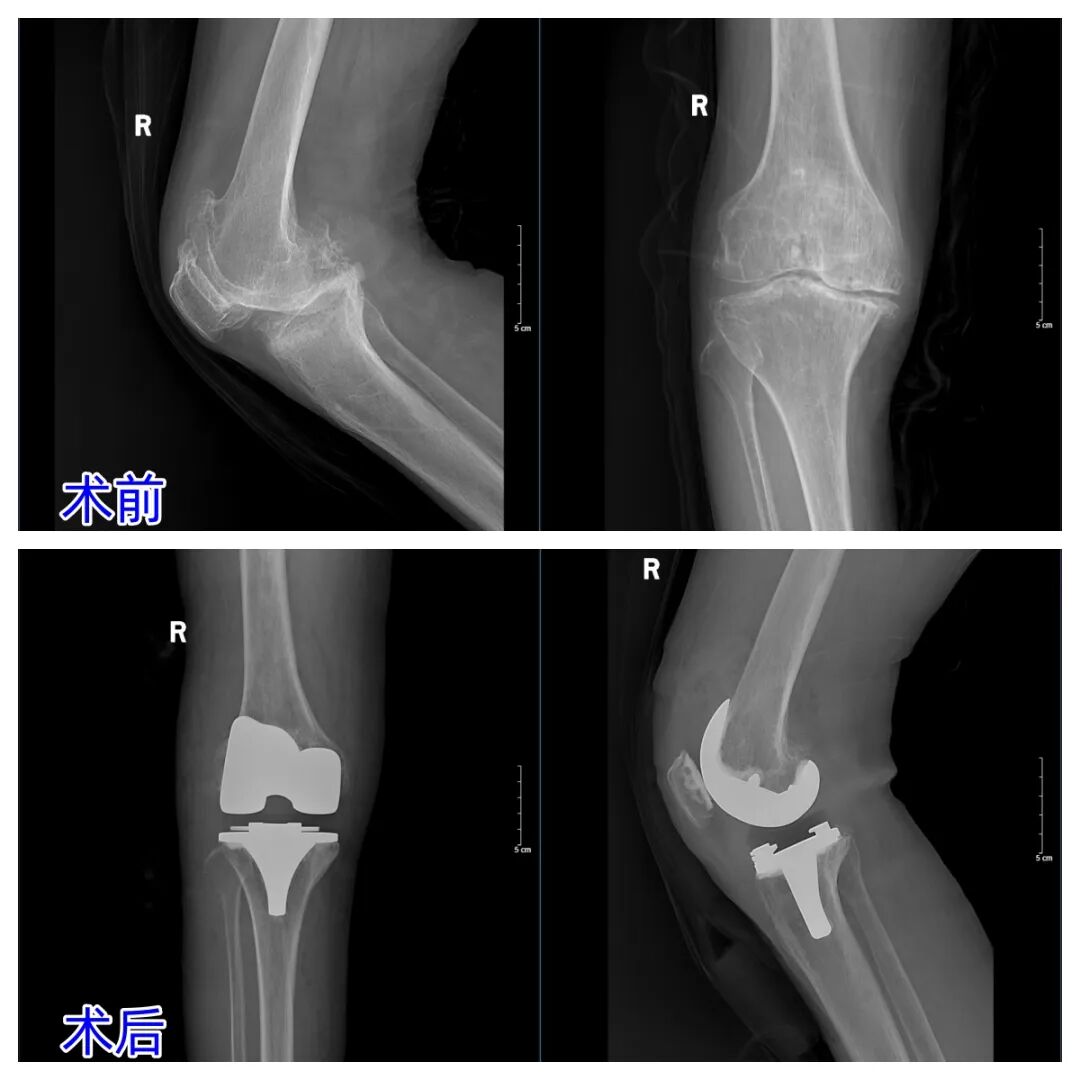

66岁张阿姨(化名)右膝疼痛20多年,起初久走隐痛,后发展成严重膝内翻畸形,关节僵硬,下蹲、起身困难。口服药物、外用膏药效果不佳。她慕名到济南南郊医院骨科,杨学良主任确诊为骨性关节炎4级,给出方案——全膝关节置换术可解决问题。

术中,杨主任用独创的内侧副韧带深度松解技术精准平衡关节间隙,安装假体后即刻矫正畸形。

术后3天,老人膝关节活动度接近正常,能轻松迈步。膝关节骨性关节炎是中老年人“隐形杀手”,拖得越久畸形越重。杨主任提醒,早诊早治是关键,晚期严重畸形患者,人工关节置换可快速“重启”关节功能,告别疼痛束缚。